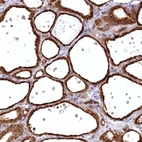

Immunohistochemical staining of human thyroid gland shows strong cytoplasmic and nuclear positivity in glandular cells.